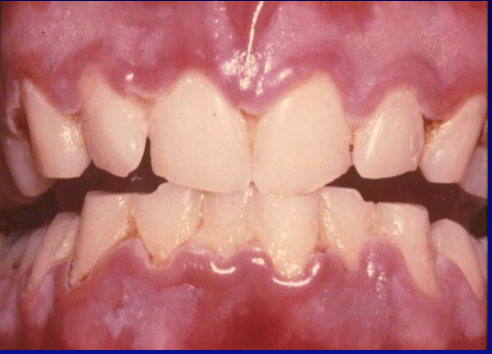

Necrotizing Ulcerative Gingivitis (NUG)

infection characterized by gingival necrosis presenting as “punched-out” papillae, with gingival bleeding and pain and foul smell

necrotizing periodontal disease

treatment: local debridement, oral hygiene instructions, oral rinses, pain control, antibiotics, modify predisposing factors, proper follow-up

the treatment of the necrotizing periodontal diseases is divided into two phases: acute and comprehensive follow up